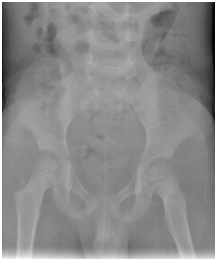

As part of primary survey patient’s chest and pelvis X-rays done at trauma bay shows no abnormality. AP and lateral X-rays of left femur showing hip and knee joints were reviewed by different ranked orthopaedics surgeons with agreement of normal x-ray impression (Figure 1 & 2). The following visits for the same complain has different x-rays with same impression of normal x-ray (Figure 3). Except for the one at last visit with the clinical evidence of deformity, patient has diaphysial femur fracture (Figure 4 ).

Figure 1 Anterior, posterior pelvis x-ray showing left hip.